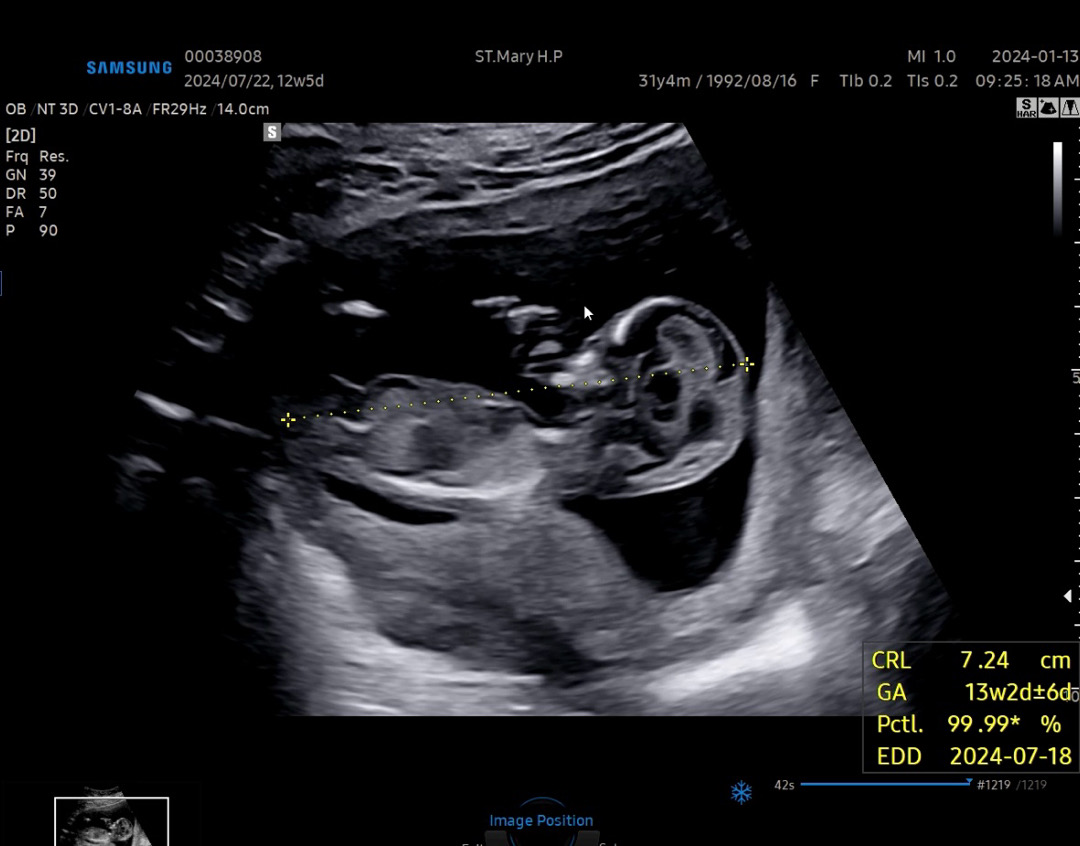

각도법 부탁드려요!

생식기쪽 잘안보여서 각도법으로 알수있으까여?